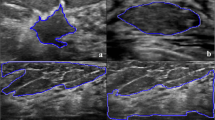

The ultrasound B-mode-based morphological and texture analysis and Nakagami parametric imaging have been proposed to characterize breast tumors. Since these three feature categories of ultrasonic tissue characterization supply information on different physical characteristics of breast tumors, by combining the above methods is expected to provide more clues for classifying breast tumors.

To verify the validity of the concept, raw data were obtained from 160 clinical cases. Six different types of morphological-feature parameters, four texture features, and the Nakagami parameter of benignancy and malignancy were extracted for evaluation. The Pearson’s correlation matrix was used to calculate the correlation between different feature parameters. The fuzzy c-means clustering and stepwise regression techniques were utilized to determine the optimal feature set, respectively. The logistic regression, receiver operating characteristic curve, and support vector machine were used to estimate the diagnostic ability.

The best performance was obtained by combining morphological-feature parameter (e.g., standard deviation of the shortest distance), texture feature (e.g., variance), and the Nakagami parameter, with an accuracy of 89.4%, a specificity of 86.3%, a sensitivity of 92.5%, and an area under receiver operating characteristic curve of 0.96. There was no significant difference between using fuzzy c-means clustering, logistic regression, and support vector machine based on the optimal feature set for breast tumors classification.

Therefore, we verified that different physical ultrasonic features are functionally complementary and thus improve the performance in diagnosing breast tumors. Moreover, the optimal feature set had the maximum discriminating performance should be irrelative to the power of classifiers.